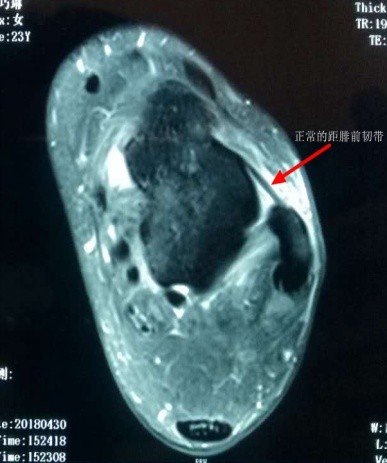

正常的踝关节核磁共振